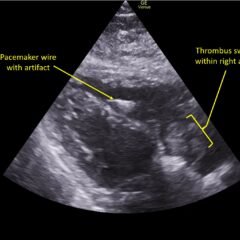

An 18-year-old female presented to the emergency department (ED) with two days of right lower quadrant pain and associated nausea and emesis. After relevant information was gathered and with physical exam findings of a tender right lower quadrant, positive psoas sign, positive Rovsing sign, and pain with right heel tap, the patient was presumed to have appendicitis. However, imaging contradicted the initial leading diagnosis and revealed a markedly distended, hydropic gallbladder with its tip near the umbilicus. Findings of the distended gallbladder with marked wall thickening and pericholecystic fat stranding and edema confirmed acute cholecystitis, and the patient was taken by general surgery for cholecystectomy. Together, this unusual presentation and this unexpected diagnosis shine light upon another facet of the hydropic gallbladder while also serving as a salient reminder to contemplate a broad differential regardless of seemingly classic presentations of illnesses.